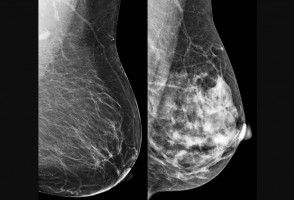

Obesidad e inflamación pueden acelerar el envejecimiento de los pulmones y aumentar el riesgo de EPOC

Un estudio con casi 900 adultos indica que, aunque el tabaquismo sigue siendo el principal factor de riesgo para la pérdida de la función pulmonar, la inflamación sistémica y la obesidad también aumentan el riesgo de desarrollar enfermedad pulmonar obstructiva crónica